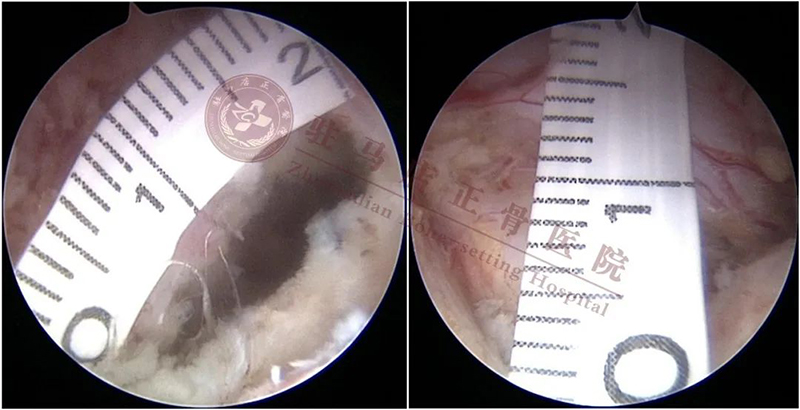

镜下测量神经根距离